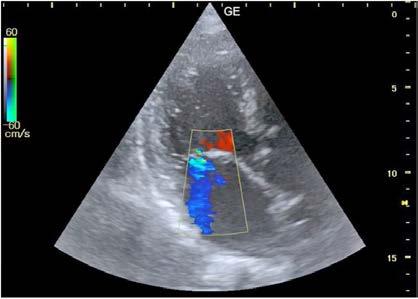

En octubre de 2024 se realizó, bajo anestesia general, cierre percutáneo de orejuela izquierda mediante acceso femoral derecho, guiado por angiografía y ecocardiografía transesofágica (ETE), y ajustando la dosis de heparina intraprocedimiento de manera estrecha (guiada por TTPA). Se implantó con éxito un dispositivo Amulet 25 mm sin complicaciones. Tras el procedimiento, se suspendió anticoagulación y valorando riesgo-beneficio, se inició antiagregación con clopidogrel, manteniendo control cardiológico y neurológico estrecho.

El paciente evolucionó favorablemente, permaneciendo estable y asintomático desde el punto de vista cardiovascular. Fue dado de alta a las 48 horas, tras confirmar adecuado posicionamiento del dispositivo en ETT. A los 45 días, el ETE de control evidenció el dispositivo de cierre de orejuela izquierda normoposicionado, sin evidenciarse flujos compatibles con leak peridispositivo mediante Doppler color. Se mantuvo el tratamiento con clopidogrel, sin registrar eventos hemorrágicos ni isquémicos posteriores.